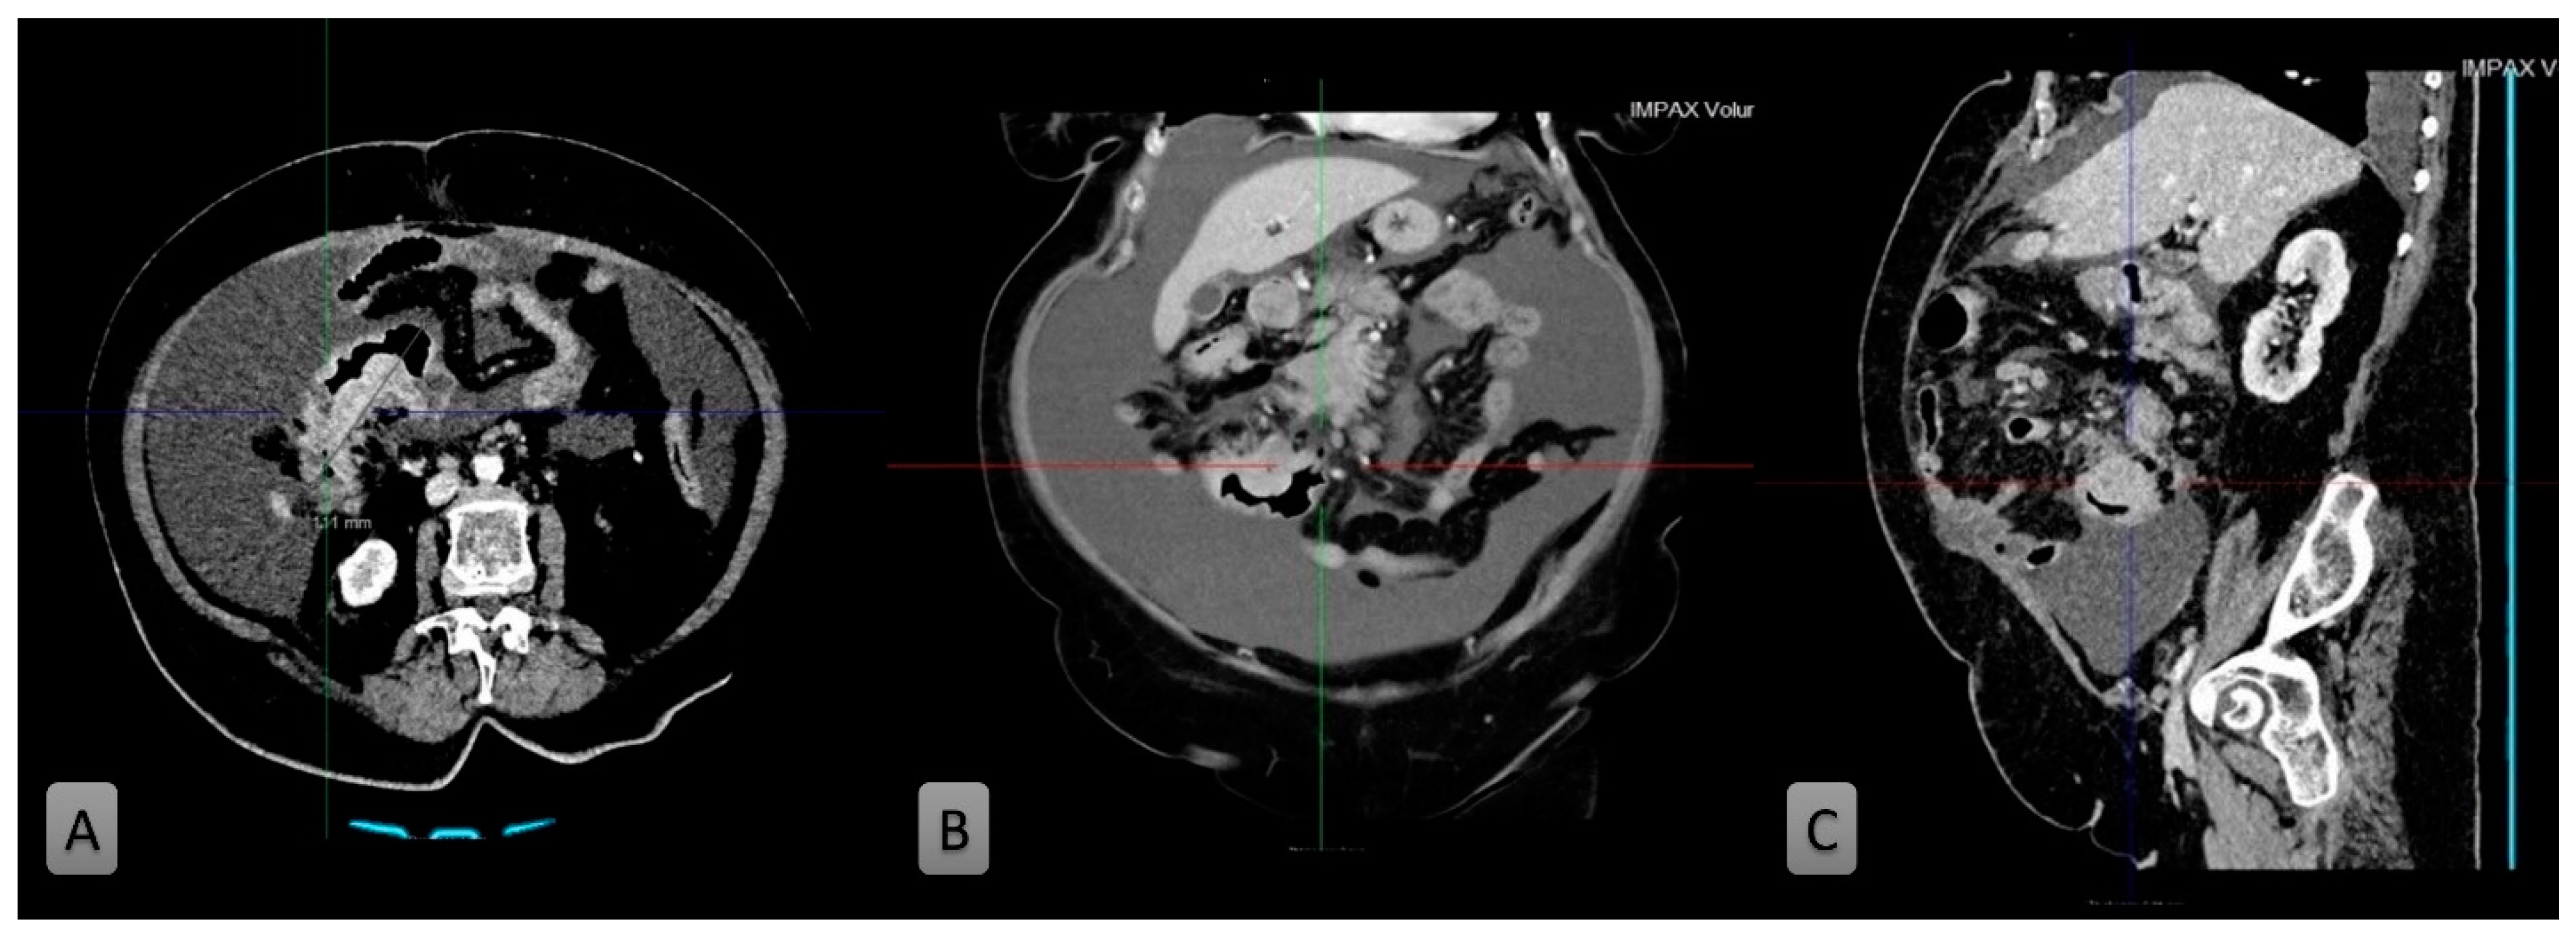

2. Case Presentation